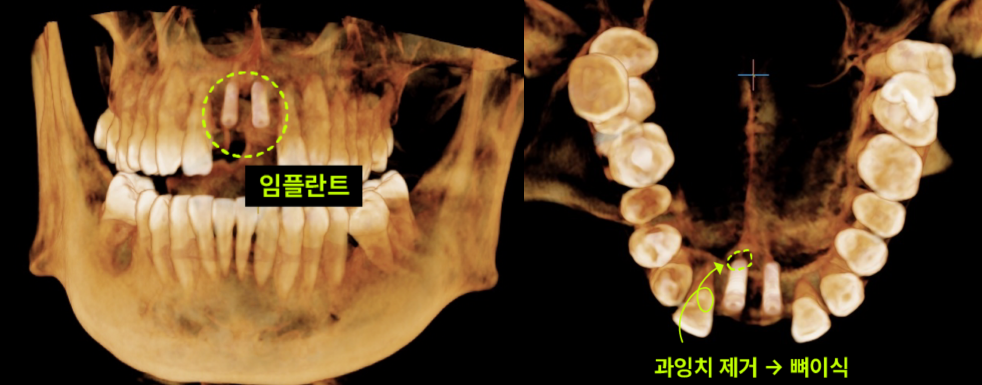

최소 침습으로 동시에 해결! 과잉치 제거&임플란트 이백점치과에서는 환자분의 부담을 줄이면서도 최상의 결과를 위해, 과잉치 제거와 동시에 임플란트 식립까지 한번에 진행하기로 치료 계획을 세웠습니다. 1. 과잉치 제거 : 입천장 잇몸을 조심스럽게 열고 잇몸 뼈를 최소한으로 삭제하여 과잉치를 안전하게 발치했습니다. 2. 동시 임플란트 식립 : 과잉치 제거 후 바로 그 부위에 임플란트를 정교하게 식립하여 수술 횟수와 치료 기간을 단축했습니다.

최소 침습으로 동시에 해결! 과잉치 제거 & 임플란트 식립 이백점치과에서는 환자분의 부담을 줄이면서도 최상의 결과를 위해, 과잉치 제거와 동시에 임플란트 식립까지 한 번에 진행하기로 치료 계획을 세웠습니다. 1. 과잉치 제거: 입천장 잇몸을 조심스럽게 열고 잇몸 뼈를 최소한으로 삭제하여 과잉치를 안전하게 발치했습니다. 2. 동시 임플란트 식립: 과잉치 제거 후 바로 그 부위에 임플란트를 정교하게 식립하여 수술 횟수와 치료 기간을 단축했습니다.

결과적으로 환자분은 기존에 모르던 매복 과잉치를 제거하고, 동시에 앞니 임플란트까지 성공적으로 마무리하여 편안하고 아름다운 앞니를 되찾을 수 있었습니다. 이처럼 과잉치 발치와 동시에 임플란트까지 진행하는 복합적인 시술은 충분한 수술 경험을 가진 의사에게 맡기는 것이 무엇보다 중요합니다. 이백점치과는 다양한 고난이도 케이스를 성공적으로 이끌어낸 풍부한 경험과 노하우 를 바탕으로, 환자분들이 믿고 맡길 수 있는 최상의 진료를 제공합니다.  |